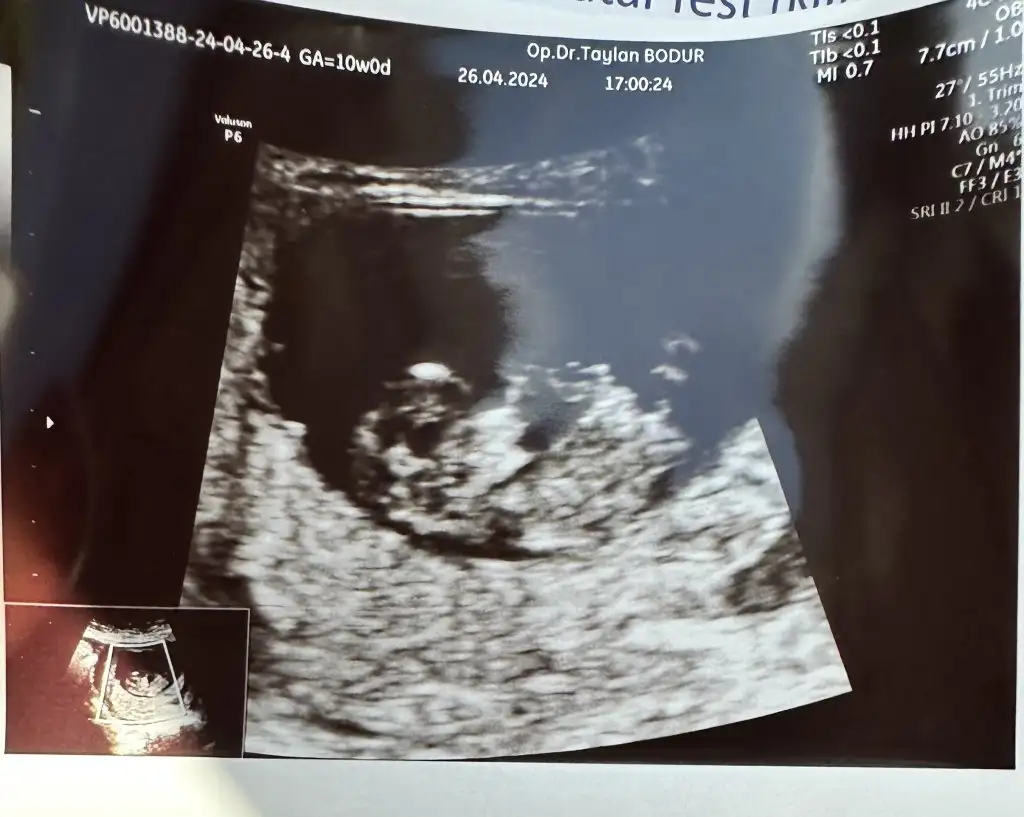

Bana da tahmin yapabilir misiniz

• IMG_3528.webp

IMG_3528.webp

17,8 KB · Görüntüleme: 58